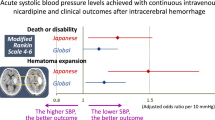

Effect of PG2 on the percentage of good and bad GOS and mRS scores in patients with acute spontaneous ICH

The percentage of good and bad GOS scores at B, W1, W4 and W12 did not differ significantly between CG and TG (all p > 0.05; Table 2).

The percentage of good and bad mRS scores at B, W1, W4, and W12 did not differ significantly between the CG and the TG (all p > 0.05; Table 2).